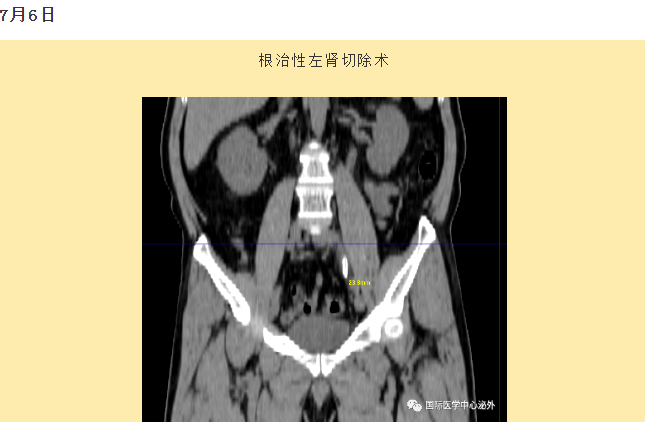

西安國際醫(yī)學(xué)中心醫(yī)院順利完成了達(dá)芬奇Xi(第四代)機(jī)器人裝機(jī)。7月6日—7月15日,泌尿外科成功完成了達(dá)芬奇Xi(第四代)機(jī)器人手術(shù)6例,標(biāo)志著科室微創(chuàng)外科邁入新時(shí)代,造福萬千患者。